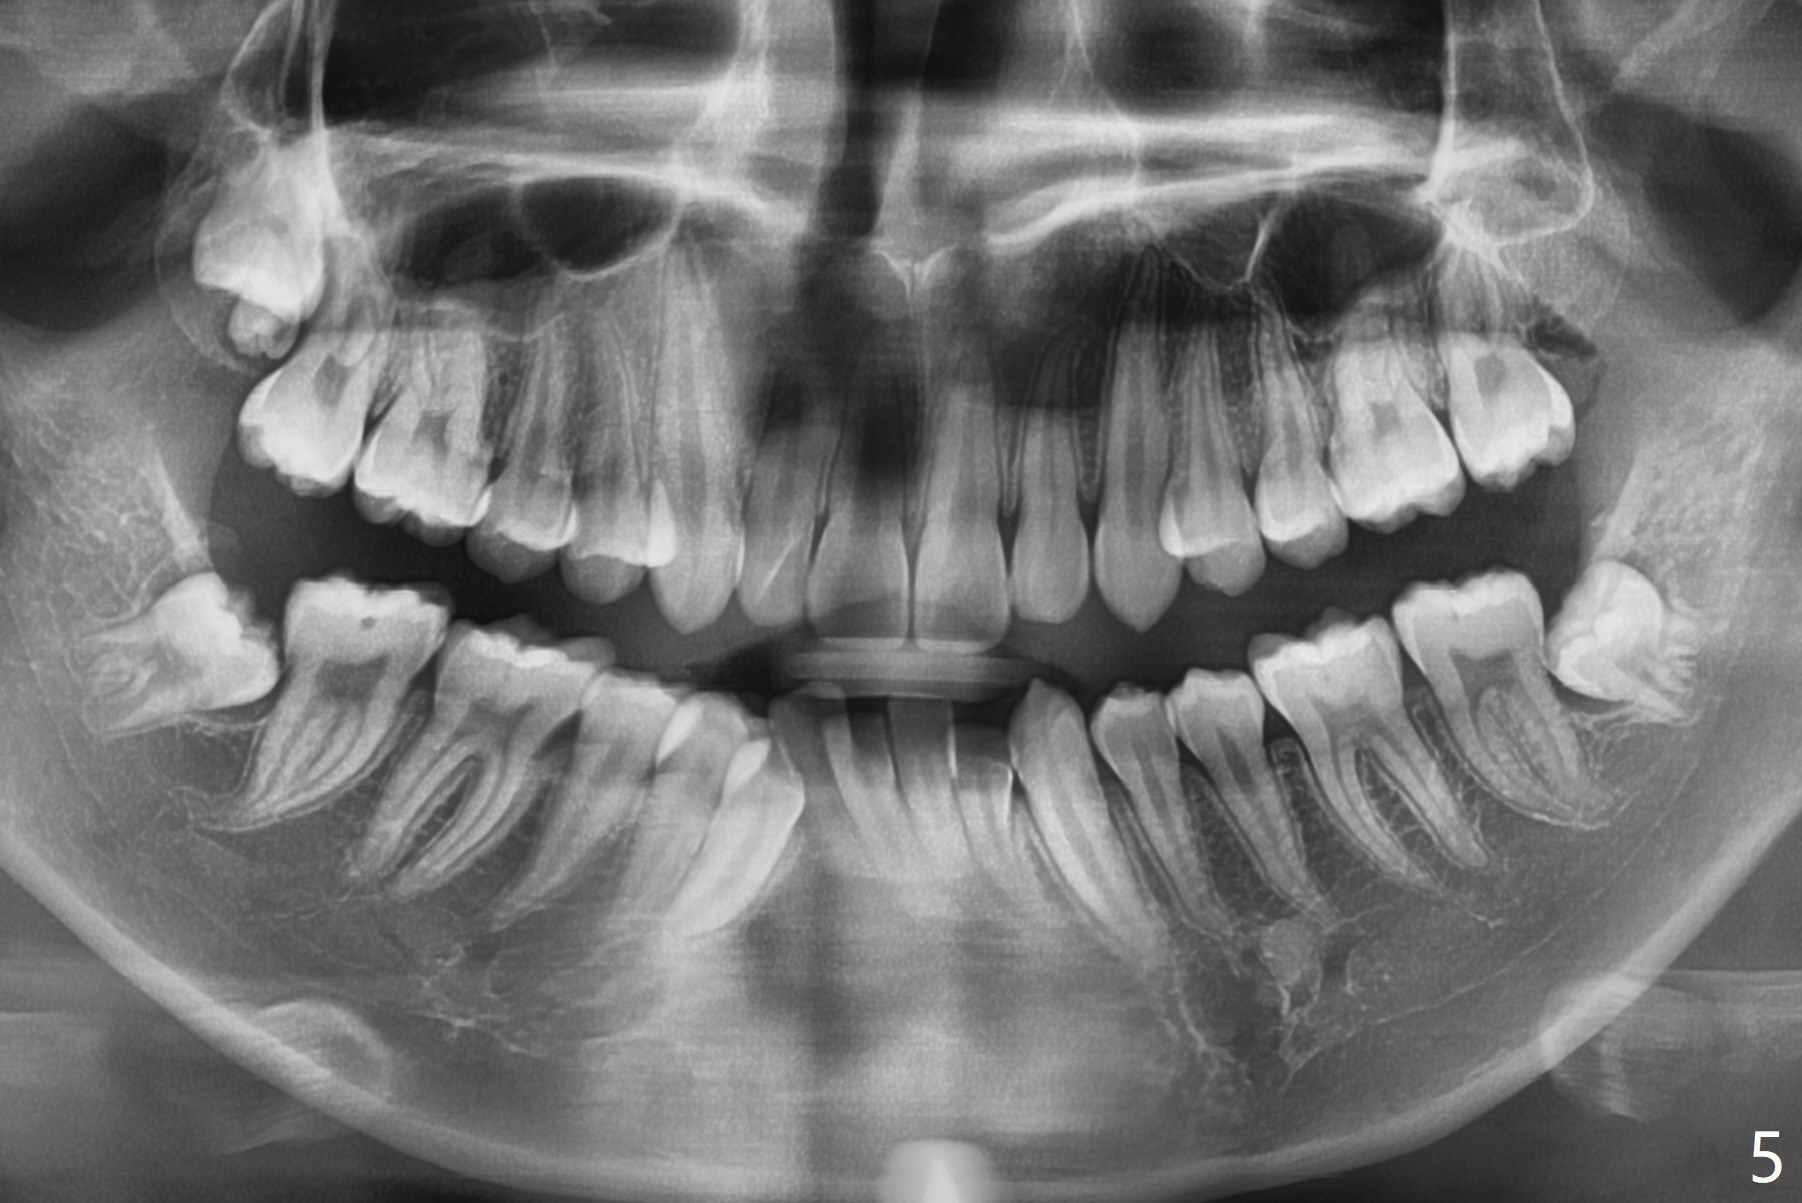

A 15-year-old man requests orthodontic treatment and agrees with extraction.  It appears that the maxilla is more protrusive than the mandible (Fig.1-4, 6,8).  The lower right canine has severe gingival recession (Fig.6,7,10).  Can we extract U4s and LR3 or 2 instead, considering relatively normal alignment in LL (Fig.8, occlusal view)?

Hi Xin, If the patient is protrusive enough (and Class I) to warrant extraction therapy, you will extract one dental unit in each quadrant, normally all four 4s. The wild card in this case is the LR3 recession and the root length being no better than the LR4. So, I would consider extraction of U4s, LL4, and LR3. Bottom line, your LR4 becomes your canine in this case.  Tim Monday, February 5, 2018 9:15 AM

In fact, extraction of LR3 is easier than the other three, because of its labial socket (Fig.10 * (loss of the labial plate), as compared to Fig.9).  Nevertheless, the root of LR3 is the longest (Fig.11).